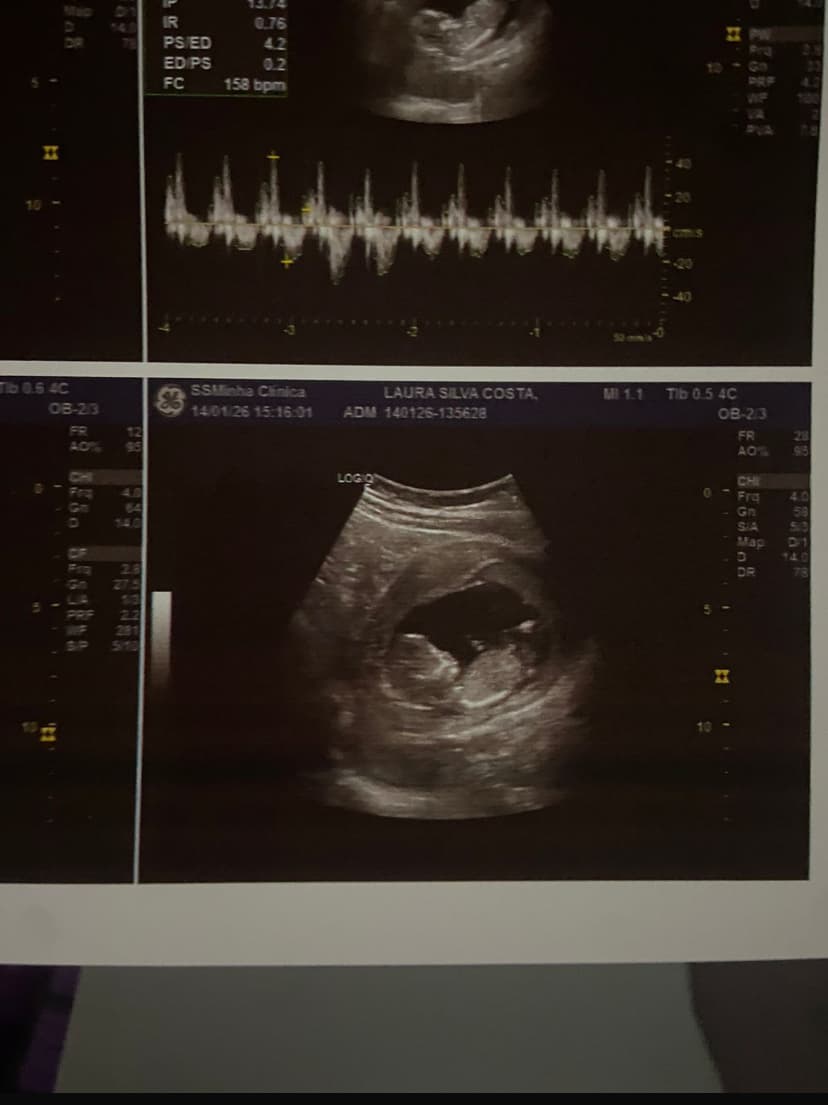

14 de janeiro de 2026

Seja uma menina 🧡